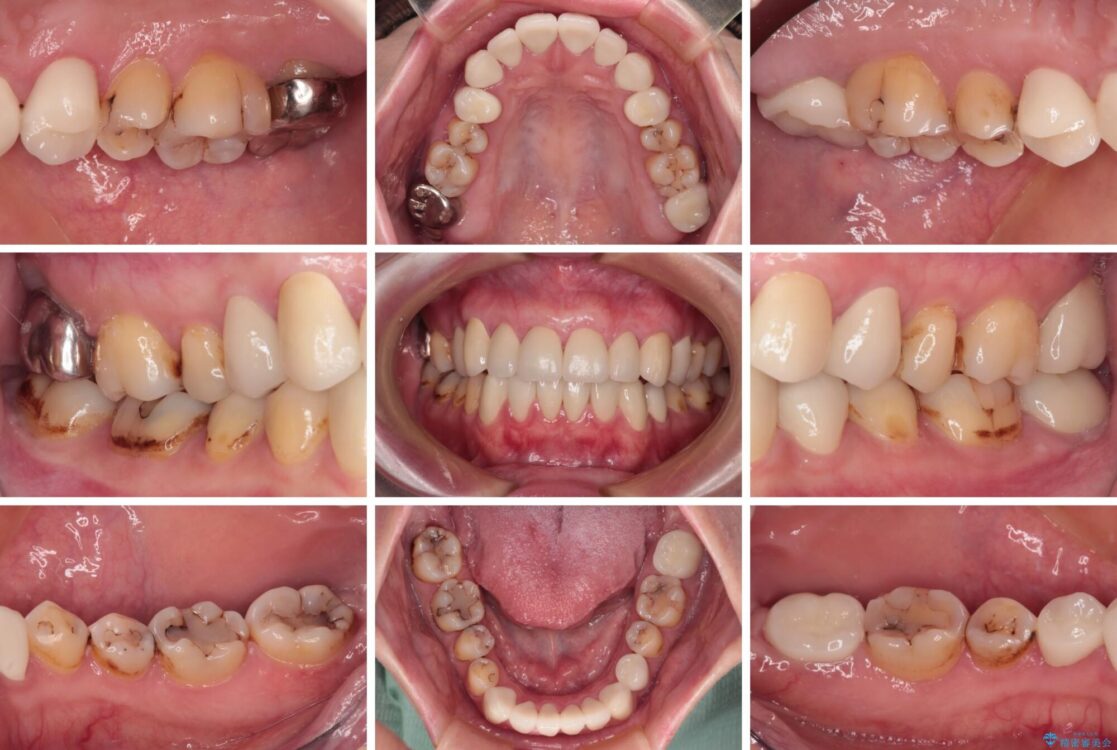

上下前歯や奥歯の虫歯治療を希望して来院された患者様です。

全顎的にむし歯が多く、根管治療の必要な奥歯や、審美的に気になっている前歯を中心にオールセラミッククラウンにて補綴治療を行うこととしました。

上顎前歯は歯肉退縮により歯根が露出していたため、事前に歯肉移植術により根面被覆を行い、その後にオールセラミッククラウンを装着することとしました。

治療後について

歯肉移植術による根面被覆を行うかどうかは非常に悩まれていましたが、歯肉が覆われたことで長く見えていた歯の長さが整い、きれいな前歯の仕上がりとなりました。

治療途中

• むし歯だらけの前歯をオールセラミッククラウンできれいに 治療途中画像

治療後

• むし歯だらけの前歯をオールセラミッククラウンできれいに 治療後画像